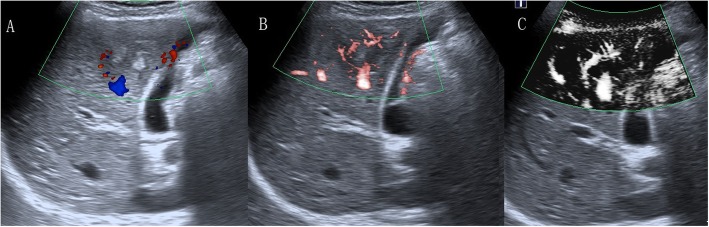

Fig. 4.

A 58-year-old woman with hepatocellular carcinoma. a CDFI showed three short-like blood flow signals (grade 2). b cSMI showed hypervascular supply in and surrounding the liver mass (grade 3). c mSMI showed residual-root flow signal pattern (the red arrow illustrates that the dilated vessel was divided into two slender vessels, pattern E)